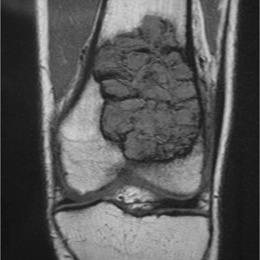

Radiographic imaging is used to help form a diagnosis. These include X-Ray, MRI, CT and Bone Scans.

An example of a Giant Cell Tumor X-Ray is shown.